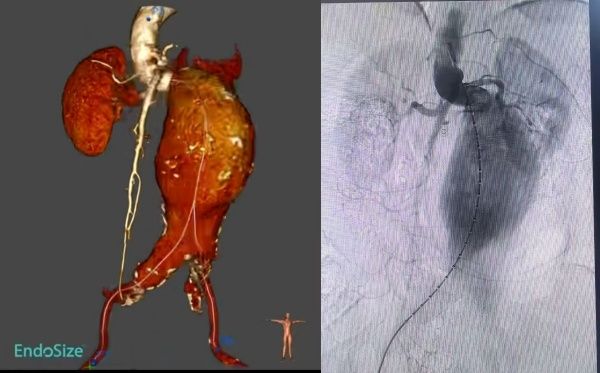

比如剧烈、持续、新发或突然改变的腹部或腰背部疼痛:这是最常见的,也是最关键的警示信号;腹部或腰部剧烈压痛/搏动性包块:患者可能会感到腹部的搏动性包块(瘤体)有明显的压痛,甚至疼痛剧烈到不让触碰;以上典型症状该患者均有着明显的表现。先兆破裂≠小破裂≠稳定状态:是即将发生灾难性大破裂的危险状态。该患者检查后提示:腹主动脉瘤样扩张至正常的三倍,瘤体大小约8cm×13㎝大小。理论上小动脉瘤(直径<5.5cm)且无破裂风险加速证据(生长不快、无症状)可密切监测风险并控制风险因素。大动脉瘤(≥5.5cm)或有症状/增长快/即将破裂,需尽快进行外科修复(开放或腔内手术修复)。该患者瘤体体积,已经远远大于常见动脉瘤体积,也是迄今为止我科室接收的腹主动脉瘤,瘤体体积最大的案例。与此同时患者还出现腹部触痛,肉眼可见的搏动,以及持续性的上腹部疼,血管外科的每一位医护人员都深切地知道,这是一场真正与死神博弈的硬仗。

在血管外科马建仓主任的有力调度下,各专业各司其职,在最短的时间内完成必要的检查以及术前准备工作。虽然时值周末,但是患者的病情刻不容缓,血管外科团队在影像科的协助下顺利为患者实施了介入手术,运用娴熟的技术,为患者成功隔绝瘤体。在手术过程中,由于患者瘤体体积非常大、整体扭曲非常严重、瘤颈短非常严重、极限铆定、重重困难均在扎实的技术前被一一突破,支架置入完成后,通过造影确认完全隔绝无内漏发生。血管外科医护人员用2个小时紧张激烈的奋战,为患者成功排雷,术后24小时即下床活动,行动自如。